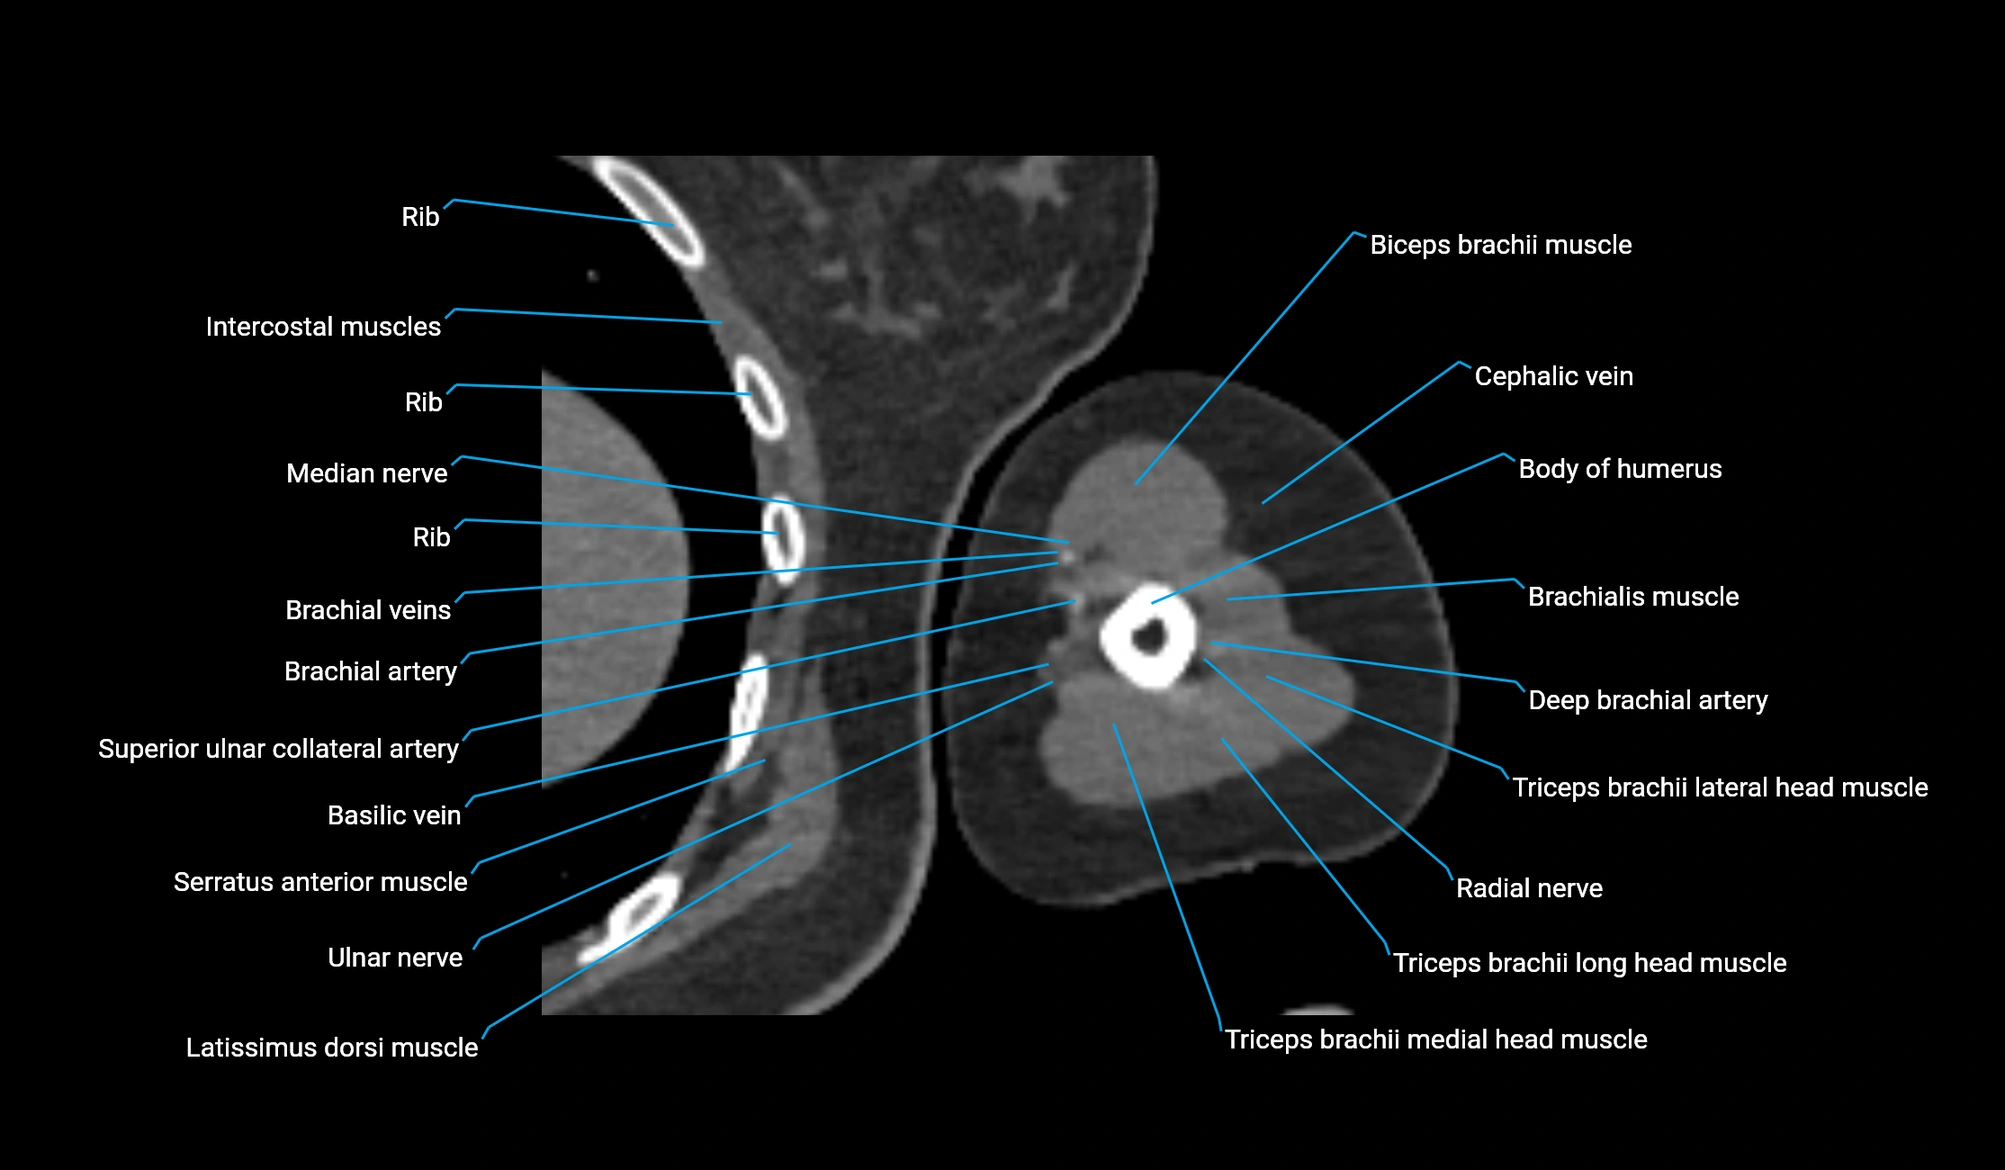

- Biceps brachii muscle

- Brachialis muscle

- Body of humerus

- Cephalic vein

- Brachial artery

- Basilic vein

- Median nerve

- Radial nerve

- Ulnar nerve

- Long head of triceps brachii muscle

- Lateral head of triceps brachii muscle

- Medial head of triceps brachii muscle

- Deep brachial artery

- Superior ulnar collateral artery

- Latissimus dorsi tendon